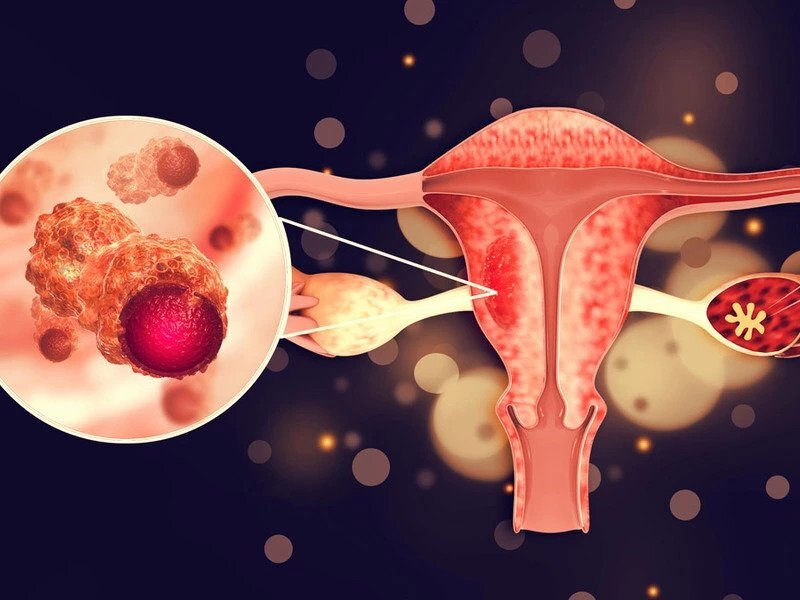

2 - کدام افراد در معرض خطر سرطان رحم قرار دارند؟

برخی از افراد جوان با وزن بالا در معرض ابتلا به سرطان رحم بوده و افرادی که اضافه وزن دارند ممکن است در سنین باروریشان به این سرطان دچار شوند. - به گزارش اقتصادنیوز به نقل از مهر، اعظم ...

3 - سرطان رحم بیشتر در این افراد دیده می شود

افرادی که اضافه وزن دارند ممکن است در سنین باروریشان به این سرطان دچار شوند. - به گزارش سلام مو به نقل از مهر، اعظم السادات موسوی متخصص فلوشیپ و انکولوژی زنان در رابطه با سرطان علائم ...

4 - این افراد در معرض خطر سرطان رحم هستند

برخی از افراد جوان با وزن بالا در معرض ابتلا به سرطان رحم بوده و افرادی که اضافه وزن دارند ممکن است در سنین باروریشان به این سرطان دچار شوند. - اعظم السادات موسوی متخصص فلوشیپ و انکولوژی ...

5 - اختلال در سیستم باروری، اولین عارضه سرطان دهانه رحم

یک متخصص فلوشیپ و انکولوژی زنان گفت: افرادی که به سرطان دهانه رحم مبتلا می شوند اولین و شایع ترین عارضه ای که برایشان پیش می آید اختلال در سیستم باروری شان است، - یک متخصص فلوشیپ و انکولوژی ...

6 - کدام افراد در معرض خطر سرطان رحم قرار دارند؟

برخی از افراد جوان با وزن بالا در معرض ابتلا به سرطان رحم بوده و افرادی که اضافه وزن دارند ممکن است در سنین باروریشان به این سرطان دچار شوند. - اعظم السادات موسوی در رابطه با سرطان علائم ...

7 - کدام افراد در معرض خطر سرطان رحم قرار دارند؟

برخی از افراد جوان با وزن بالا در معرض ابتلا به سرطان رحم بوده و افرادی که اضافه وزن دارند ممکن است در سنین باروریشان به این سرطان دچار شوند. - متخصص فلوشیپ و انکولوژی زنان گفت: برخی از ...

8 - سرطان رحم در کمین زنان؛ راه های انتقال ویروس HPV و نحوه پیشگیری از آن

90 درصد موارد ابتلا به HPV از طریق غربالگری قابل پیشگیری است. - متخصص سرطان زنان گفت: 90 درصد موارد ابتلا به HPV از طریق غربالگری قابل پیشگیری است. به گزارش پارسینه؛ اعظم السادات موسوی متخصص ...

9 - 90 درصد موارد ابتلا به HPV قابل پیشگیری است

90 درصد موارد ابتلا به HPV از طریق غربالگری قابل پیشگیری است. - اعظم السادات موسوی متخصص فلوشیپ و انکولوژی زنان در گفتگو با خبرنگار مهر ، در رابطه با بیماری سرطان دهانه رحم، عوارض و علائم آن گفت:

19 - سونامی سرطان های پیشرفته زنان به دلیل کرونا

رییس انجمن متخصصین زنان و مامایی ایران با اشاره به وقوع سونامی سرطان های پیشرفته زنان به دلیل کرونا گفت: ترس از ابتلا به کرونا سبب مراجعه دیر بیماران به پزشکان و یا ناقص ماندن درمانی ...